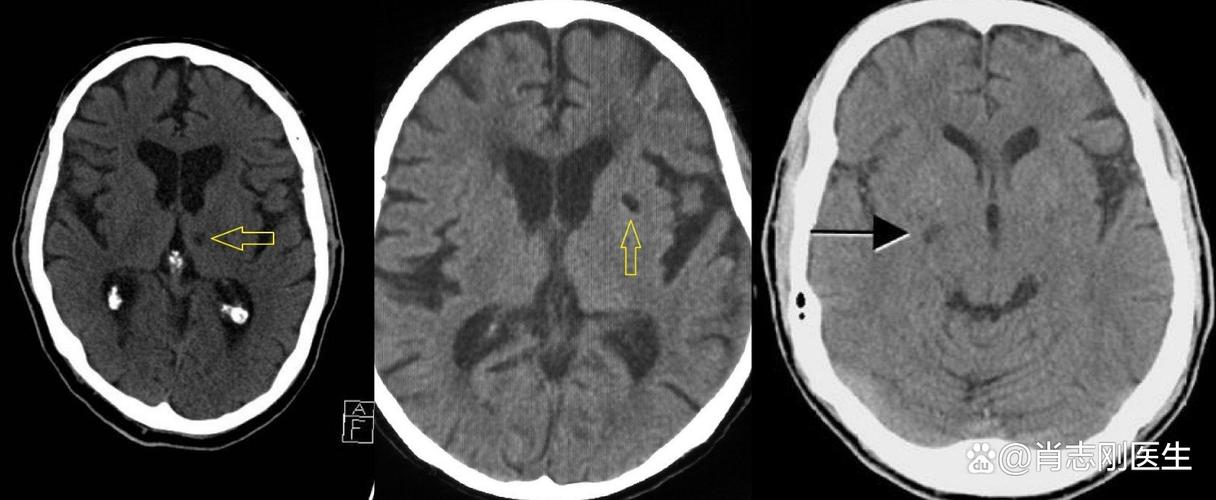

“缺血灶”和“脑腔梗”都是脑组织曾经缺血坏死的“遗迹”或“疤痕”,它们在核磁共振(MRI)上表现为信号异常的区域,是医生判断脑血管健康状况的重要依据。

缺血灶是一个比较宽泛的术语,可以把它理解为大脑某个区域曾经发生过缺血事件,并留下了一个“印记”,这个印记在影像学上表现为一个边界不清、形态不规则的异常信号区。

腔隙性脑梗塞是缺血灶中一个特定类型,有非常明确的定义和特征。

- 位置:发生在大脑半球深部、脑干等部位,这些区域的血管比较细长,被称为“穿通动脉”或“终末动脉”。

- 大小:病灶非常小,直径通常在 5毫米到20毫米 之间。

- 形态:病灶形态相对规则,呈圆形或卵圆形,像个小“豆子”或“小坑”。